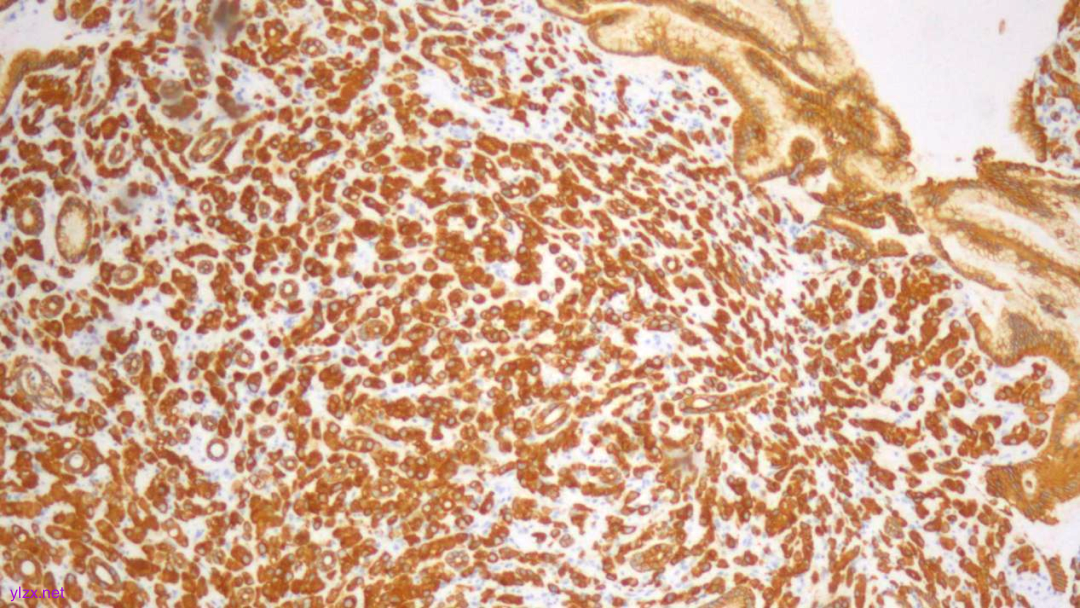

IHC结果:

P120(浆+),P16(灶+),P53(野生型表达),Her2(1+),CK7、GATA3、GCDFP-15、CK-H均(+),ER、PR、E-Cadherin、CK20均(-),Ki67(约5%+)

GCDFP-15(弥漫+)

GATA-3(+)

CK7(弥漫强+)